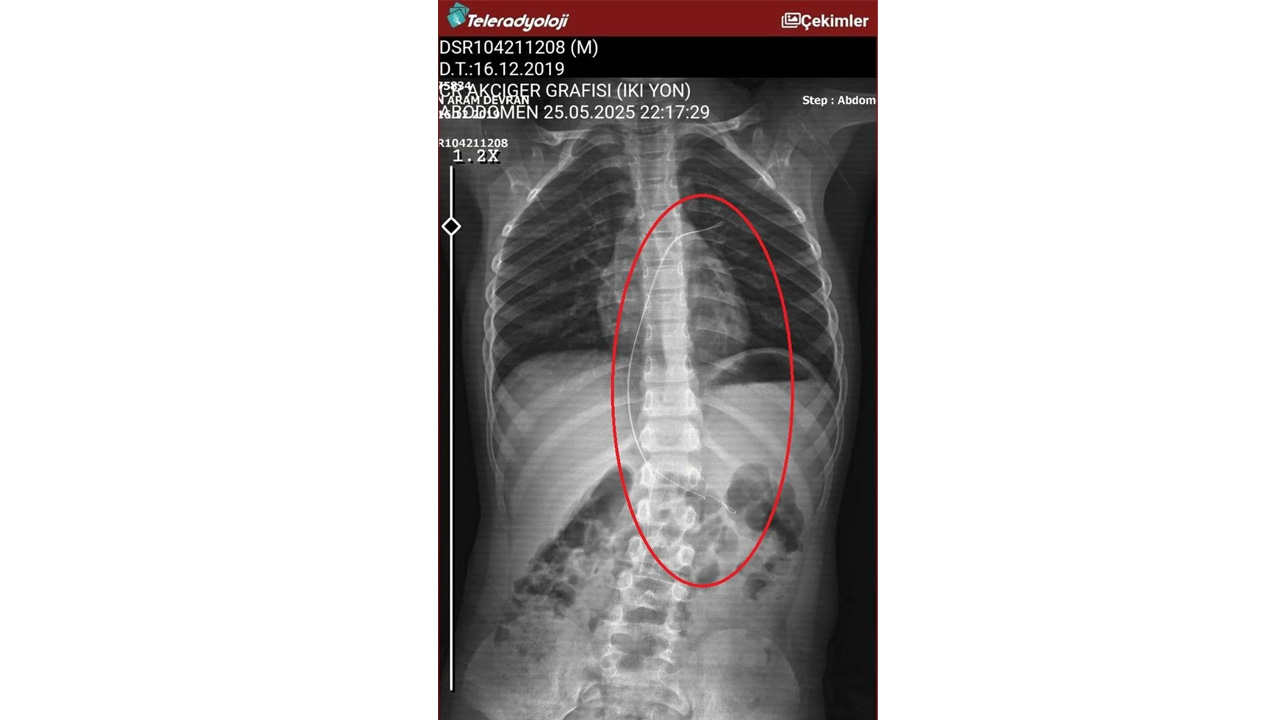

Burada çekilen röntgen ve MR'da Aram'ın vücudunda kateter unutulduğu görüldü.

Diyarbakır'daki Gazi Yaşargil Eğitim ve Araştırma Hastanesi Kadın Doğum ve Çocuk Ek Binası'na sevk edilen Aram, 5,5 saat süren riskli bir ameliyata alınarak 18 santimetre uzunluğundaki kateter çıkarıldı.

Ameliyat sonrası yapılan incelemelerde kateterin kalp kapakçığına ve ciğerlerine zarar verdiği belirlendi.

Gece saatlerinde çocuklarını hastaneye götürdüklerini anlatan anne, "Doktor röntgeni gösterdi. Tel kalmıştı. Çok kötü bir şekilde. Acil doktoru film çektikten sonra bize bir tel parçasını gösterdi. Bizi bekletmeden Diyarbakır’a sevkimizi verdiler." dedi.